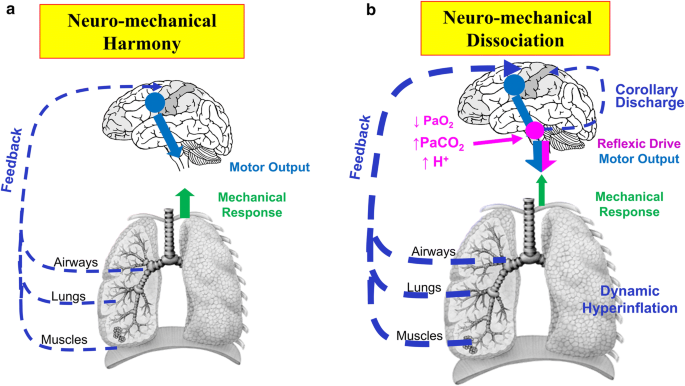

With normal breathing the diaphragm pulls downward and the lungs expand fully. Recovery of diaphragm strength is more variable than recovery of upper limb function and typically takes 25 years12 Although no treatment. Lung cancer and other tumors.

The rise in intraabdominal pressure further increases intrathoracic and lung volume by pushing the lower rib cage outward. In severe cases when there is no simple treatment that can relieve dyspnea your doctor may prescribe morphine. Diaphragmatic dysfunction caused by transverse myelitis or leukemic infiltration of the cervical spinal cord in a patient with leukemia and shortness of breath. Diaphragmatic plication a surgical procedure that pulls the diaphragm down by introducing a repeated series of continuous sutures across the diaphragm and pulling the muscle taut. A bedside fan or open window with a breeze are also simple but very effective treatments to lessen dyspnea. Depending on the severity of injury to the diaphragm some doctors recommend non-surgical options to treat the breathing issues associated with diaphragm weakness and paralysis. P E Pulmonary embolism.